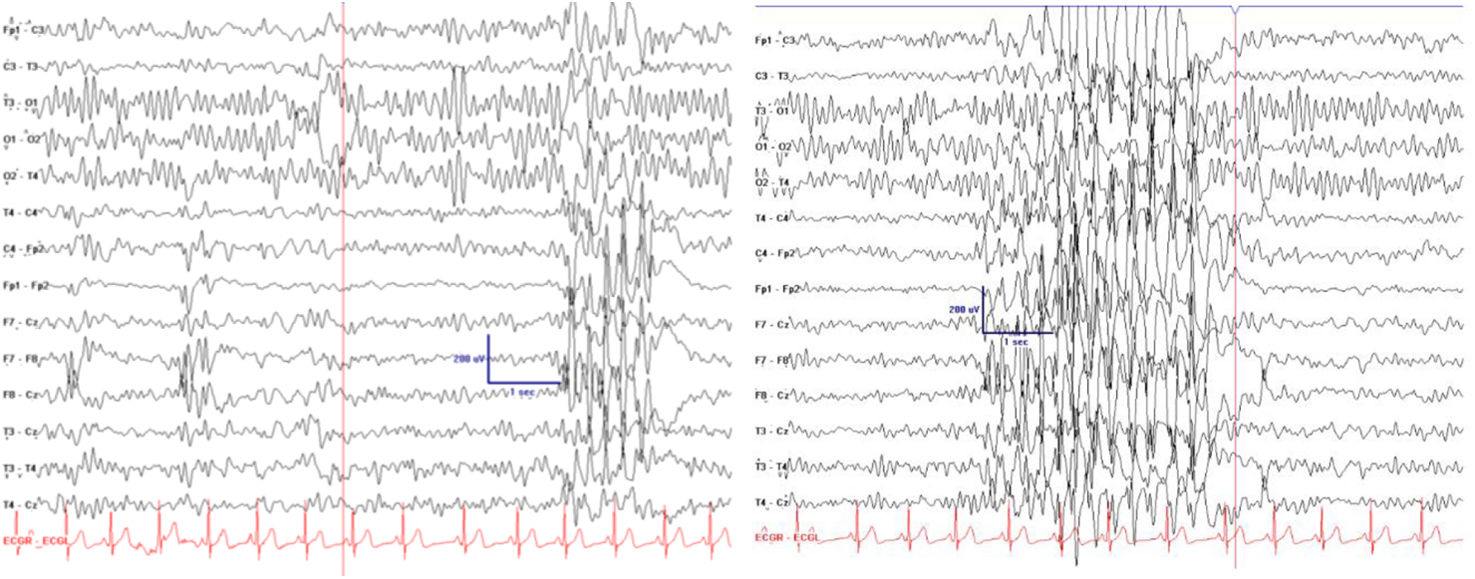

Our sample included 94 patients (45 boys and 49 girls) with typical absence seizures, with a median age of epilepsy onset of 8.6 years (Q1-Q3: 6-10.1). Eighty-four percent of patients presented exclusively absence seizures. In 14 cases (14.8%), frontal activity preceded the spike-and-wave discharge (Fig. 1); these patients were classified as having FAE with SBS. MRI studies were performed in 54 patients, yielding normal findings in all cases. Regarding EEG, the hyperventilation manoeuvre triggered seizures in 94.2% of patients, with no significant differences between the FAE and PAE groups. Intermittent photic stimulation induced a photoparoxysmal response in 5.3% of patients. Focal paroxysmal activity was observed in 63 patients, with 45 showing activity localised in the frontal lobe.

Figure 1.

Frontal paroxysmal activity characterised by a spike-and-wave pattern in the right anterior frontotemporal region, with secondary generalisation as spike-and-wave discharges at 3.5-4 Hz.